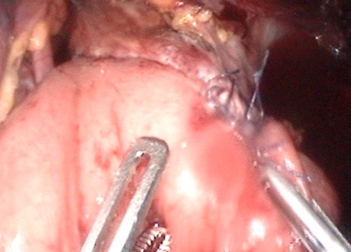

右のような手順で小腸と食道をつなぎ合わせます。

小腸にホチキスを入れ・・・

食道にもホチキスを入れ・・・

ホチキスを閉めてハンドルを操作すると・・・

食道と小腸が縫い付けられると同時に、間が切り開かれて、食道と小腸が筒状につながります。

ここで食道を切り離し、胃が全摘されます。

ホチキスを入れた穴はおなかの中で縫い合わせます。